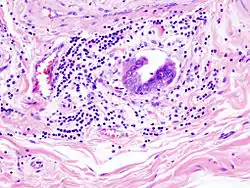

Gallbladder adenocarcinoma lymphatic invasion histopathology

Incidentally discovered gallbladder cancer (adenocarcinoma) following a cholecystectomy.

Gallbladder adenocarcinoma histopathology